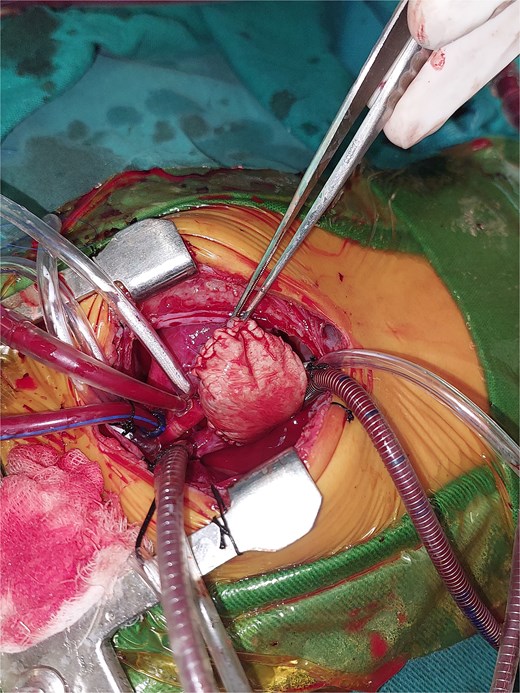

A 2-month-old female infant was admitted with respiratory distress characterized by tachypnea, and cough, along with poor feeding and systemic symptoms such as fever and episodic diaphoresis. At 25 days of age, she had previously been hospitalized for similar symptoms, during which a massive pericardial effusion was identified. Initially, an extracardiac mass was suspected. Despite undergoing two pericardiocenteses and resuscitation after two post-cardiac arrest events, her clinical status continued to deteriorate, and she was referred for urgent surgical intervention due to cardiogenic shock from pericardial tamponade. On examination, she appeared pale with respiratory distress, intercostal retractions, pulsatile hepatomegaly (2 cm), splenomegaly (1 cm), and tachycardia (160 bpm). Laboratory findings showed hyponatremia (125 mmol/L). TTE demonstrated cardiomegaly, bilateral pleural effusion, and a massive pericardial effusion measuring 24–28 mm circumferentially. A 2.7 cm mass adjacent to the anterior RA wall and atrioventricular (AV) groove was identified (Fig. 1). Due to her unstable condition, CT imaging was deferred. An emergent median sternotomy revealed a severely distended pericardium containing copious effusion (Fig. 2). Upon opening the pericardium, immediate hemodynamic improvement was observed. The mass was visualized infiltrating the RA anterior wall and AV groove (Fig. 3). Total cardiopulmonary bypass (CPB) was initiated using aortic and bicaval cannulation. Following cardiac arrest with antegrade cold blood cardioplegia, the RA was incised posterior to the tumour. The lesion extended beyond the AV groove, precluding complete excision due to anatomical constraints (Fig. 4). Subtotal (debulking) resection was performed (Figs 4 and 5), and the RA anterior wall was reconstructed with a bovine pericardial patch (Fig. 6). The patient was successfully weaned from CPB, and the remainder of the surgery was uneventful. The infant was extubated within 48 hours and discharged after a 14-day hospital stay, with subsequent TTE showing satisfactory cardiac function. Histopathological evaluation confirmed a benign capillary hemangioma characterized by lobulated reddish tissue with compact capillary proliferation, fibrous septae, and stromal hyalinization. Immunohistochemical staining was positive for CD31 and CD34, confirming endothelial origin and ruling out malignancy (Fig. 7). At one-year follow-up, the patient remained in excellent general health with no signs of recurrence.

Intraoperative image showing the stretched pericardium due to massive effusion.